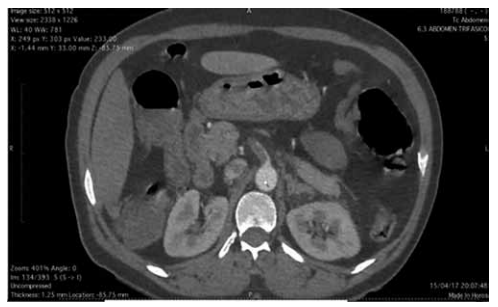

Mulher de 78 anos, hipertensa e fibrilação atrial crônica, sem anticoagulação, apresenta dor abdominal difusa de início súbito há 4 horas, desproporcional ao exame físico. FC: 118 bpm, PA: 132/74 mmHg, afebril. Abdome flácido, sem sinais de peritonite. Leucograma: 18.500/mm³, D-dímero: elevado, Lactato: 4,5 mmol/L. TC de abdome com contraste demonstrada na imagem a seguir:

(Arquivo pessoal; imagem usada com autorização)